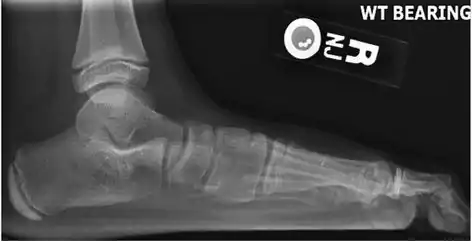

On plain radiography, flat feet can be diagnosed and graded by several measures, the most important in adults being the talonavicular coverage angle, the calcaneal pitch, and the talar-1st metatarsal angle (Meary's angle).[11] The talonavicular coverage angle is abnormally laterally rotated in flat feet.[11] It is normally up to 7 degrees laterally rotated, so a greater rotation indicates flat feet.[11] Radiographies generally need to be taken on weightbearing feet in order to detect misalignment.[12]